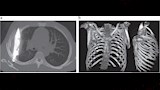

وأظهرت الفحوص السريرية أن الجزء الأيمن من صدره لا يتمدد بالكامل أثناء التنفس، فيما كشفت الأشعة السينية وجود شفرة سكين كبيرة عالقة في تجويف الصدر، ممتدة من الظهر إلى مقدمة القفص الصدري، ومحاطة بطبقات من القيح والأنسجة الميتة.

وأجرى الأطباء عملية بضع الصدر لإزالة الشفرة وتفريغ القيح وغسل التجويف بمحلول ملحي، ثم وضع أنبوب تصريف وخياطة الجرح، إذ تلقى المريض مضادات حيوية واسعة الطيف لمدة سبعة أيام، وتمت متابعة حالته على مدى أسابيع للتأكد من عدم حدوث مضاعفات.

وتسلط هذه الحالة الضوء على قدرة الجسم أحيانا على عزل الأجسام الغريبة عبر ما يعرف بـ"التغليف الليفي"، ما يفسر بقاء الشفرة طوال تلك المدة دون ظهور أعراض حادة.